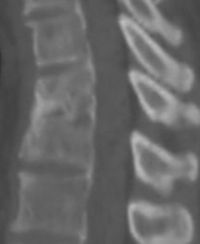

图片说明:左图为治疗前二维CT,右图为微创治疗后3年半

Bkm5m.jpg

Bkm5n.jpg

随访二维CT照片。